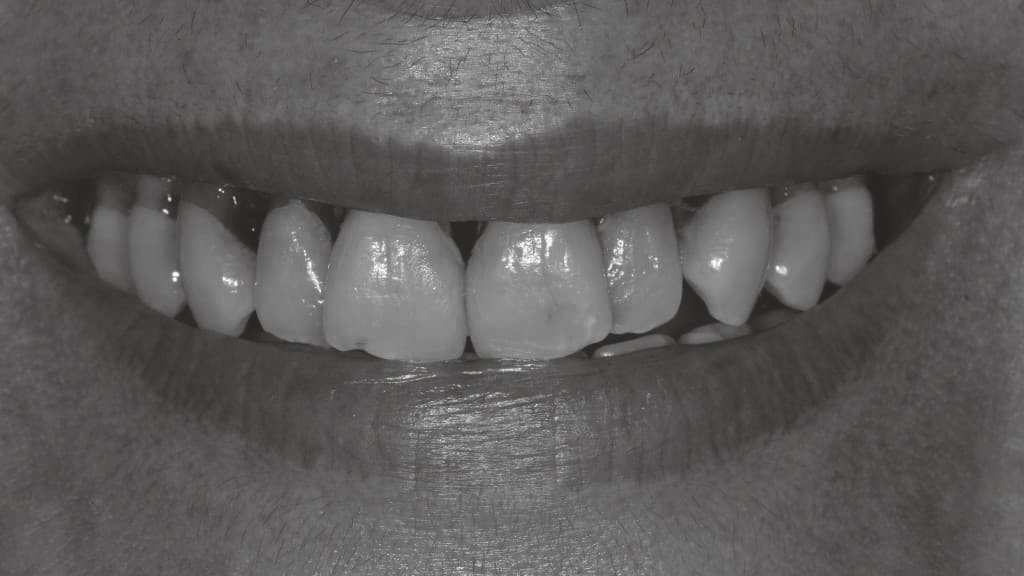

Antes y después en nuestros tratamientos dentales

A continuación te exponemos algunos de nuestros casos de antes y después en implantes dentales, ortodoncia y estética dental.

Antes y después en Implantes Dentales

En las imágenes de antes podemos ver a pacientes con dientes faltantes o dañados, lo que les dificultaba sonreír con confianza y realizar actividades cotidianas como masticar. Sin embargo, después de la colocación de los implantes dentales, podemos ver cómo sus sonrisas han cambiado completamente.